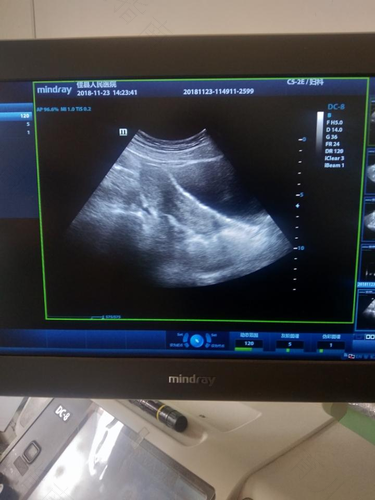

子宫对于女性来说是很重要的器官,如果女性出现子宫内膜过薄的情况,也就说明子宫健康出现了问题。子宫内膜薄可能会影响到女性正常的月经来潮,同时也不利于怀孕,那么,子宫内膜薄有什么症状呢?

子宫内膜薄,大体上分两类,一类是子宫原因导致的器质性子宫内膜薄,另一类是内分泌功能异常引起的功能性子宫内膜薄。器质性子宫内膜薄,多见于人流刮宫等手术创伤,如果手术伤到子宫基底层,常常会引起子宫内膜变薄,一般表现为经量减少,一般给予雌孕激素替代治疗,激素量大一些,让子宫内膜充分增生,一般替代几个月到半年左右就会恢复正常。